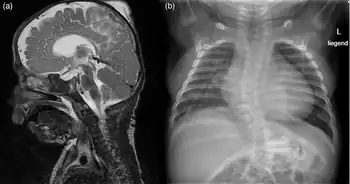

This is an X-linked condition affecting males more than females and is characterized by postnatal growth failure with developmental delays and dysmorphic features characterized by wrinkled forehead, anterior and posterior fontanels, prominent eyes, large down-slanting palpebral fissures, thickened or hooded eyelids, large ears, flared nares, hypoplastic alae nasi, short columella, protruding upper lip, and microretrognathia. There is also delayed closing of fontanelle, and the boys also have broad great toes. Skin is characterized by redundancy or laxity with minimal subcutaneous fat, cutaneous capillary malformations, and very fine hair and eyebrows. Death resulted from cardiogenic shock following arrhythmia, which was noted in all affected individuals. The boys had heart rhythm abnormalities and craniofacial abnormalities, which accounted for their similar appearance. The boys were never able to sit up on their own, and none learned how to talk.[2] They all had a characteristically aged appearance, earning them the family nickname of "little old men."[2] Several of the boys had structural anomalies of their hearts including ventricular septal defect, atrial septal defect, and pulmonary artery stenosis. Events recorded on electrocardiogram before death included torsades de pointes, premature ventricular contraction (PVC), premature atrial contraction (PAC), supraventricular tachycardia (SVtach), and ventricular tachycardia (Vtach). Most of the children had inguinal hernias, and the majority had, at least, unilateral cryptorchidism. All had neonatal hypotonia progressing to hypertonia, and cerebral atrophy on MRI; several, but not all, had neurogenic scoliosis. Death occurred prior to two years in all cases and prior to one year in the majority. There are extensive clinical details for each child reported in the original publication